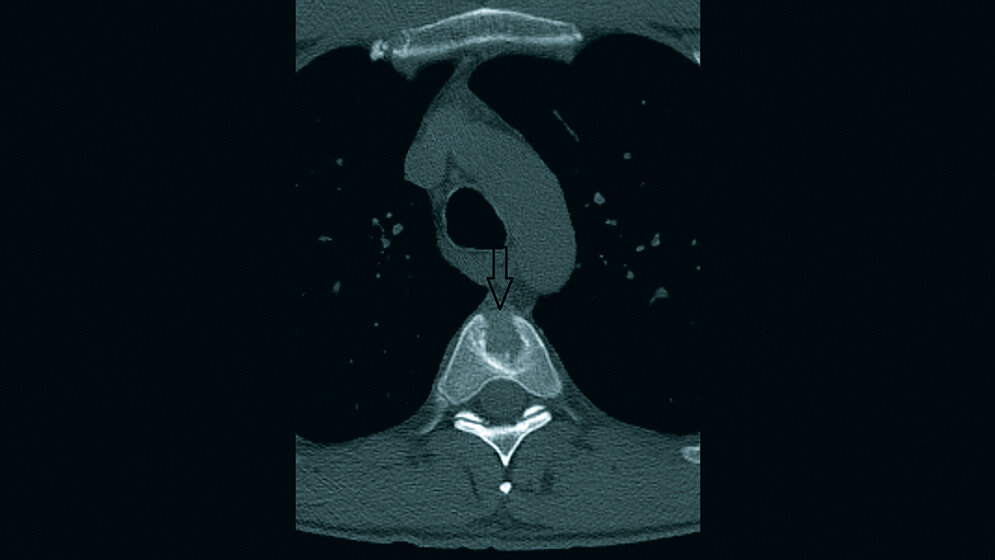

Der Schmetterlingswirbel ist eine seltene angeborene Fehlbildung der Wirbelsäule. Er wird meist als Nebenbefund gefunden und ist asymptomatisch.

Butterfly vertebra is an uncommon congenital spinal anomaly. It is considered to be incidental and usually asymptomatic.